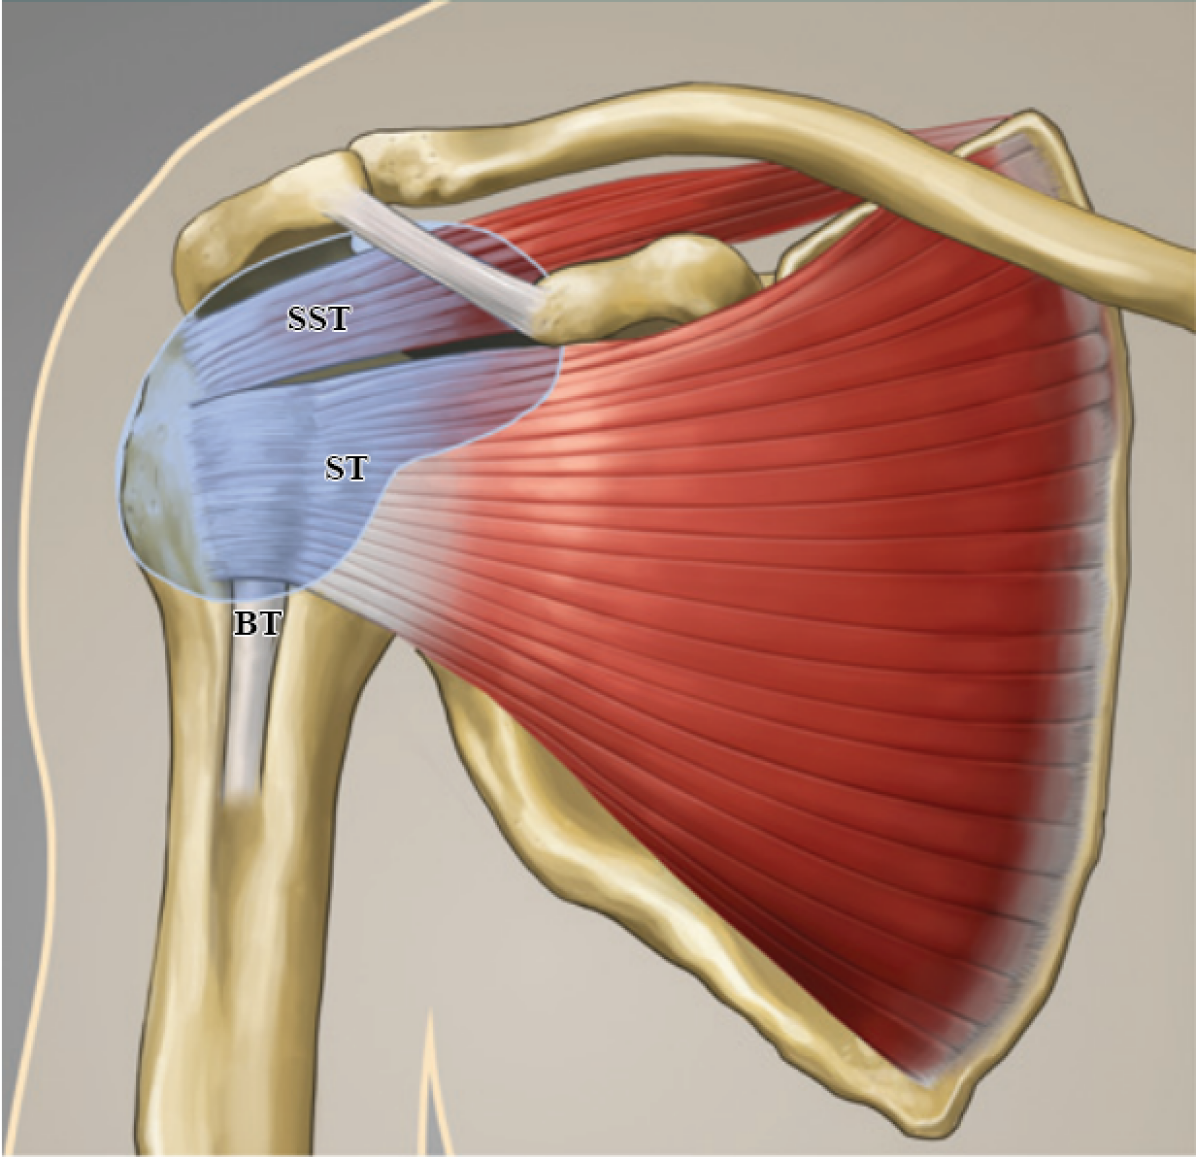

In this paper, automatic recognition of supraspinatus tendinopathy has been addressed, which refers to the minor disorders of the supraspinatus tendon (SST) in the rotator cuff. This tendon connects the supraspinatus muscle to the greater tuberosity of the proximal humerus and is located in the suprascapular fossa of the scapula inside the rotator cuff, as illustrated in Fig. 1(a). Statistics have revealed that supraspinatus tendinopathy is the most commonly encountered around the shoulder joint [1]. This condition causes “painful arc” syndrome and limits the patient hand/shoulder movements for several months. Early detection of supraspinatus tendinopathy can help to reduce the unfavorable pathological effects and to shorten the recovery time.

Figure 1: (a) illustrates the anterior view of the shoulder anatomy, showing brachii (BT), subscapularis (ST), and supraspinatus (SST) tendons (Image courtesy of Carolyn Nowak, Ann Arbor, Mich.), and (b) depicts the modified coronal view of the SST in US images of a normal case (left) and a tendinopathy case (right). The SST area is annotated with yellow dashed lines, and orange dotted lines indicate areas of tendon pathology.